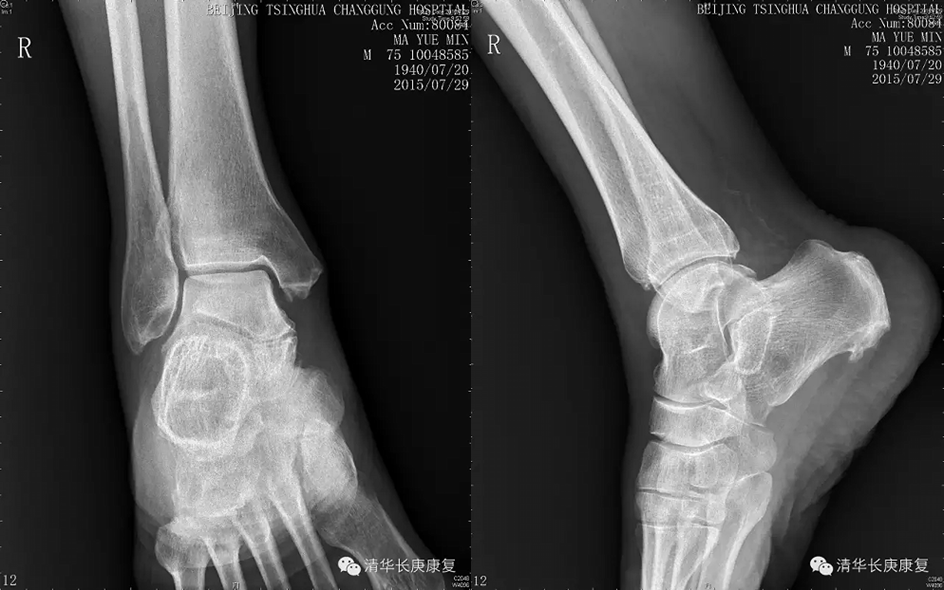

患者老年男性,主诉右侧踝部疼痛肿胀2年,加重10天。患者于2年前无明显诱因下出现右踝部疼痛肿胀,行走后加重,2年来症状反复发作,曾行封闭治疗后症状略缓解,就诊前10天无诱因出现疼痛及肿胀加重,行走受限。查体:右侧踝关节疼痛肿胀,VAS评分7分,右下肢髂腰肌、股四头肌肌力V-级,余下肢肌力V级,踝关节活动范围正常。

右踝关节X线示:踝关节退行性变